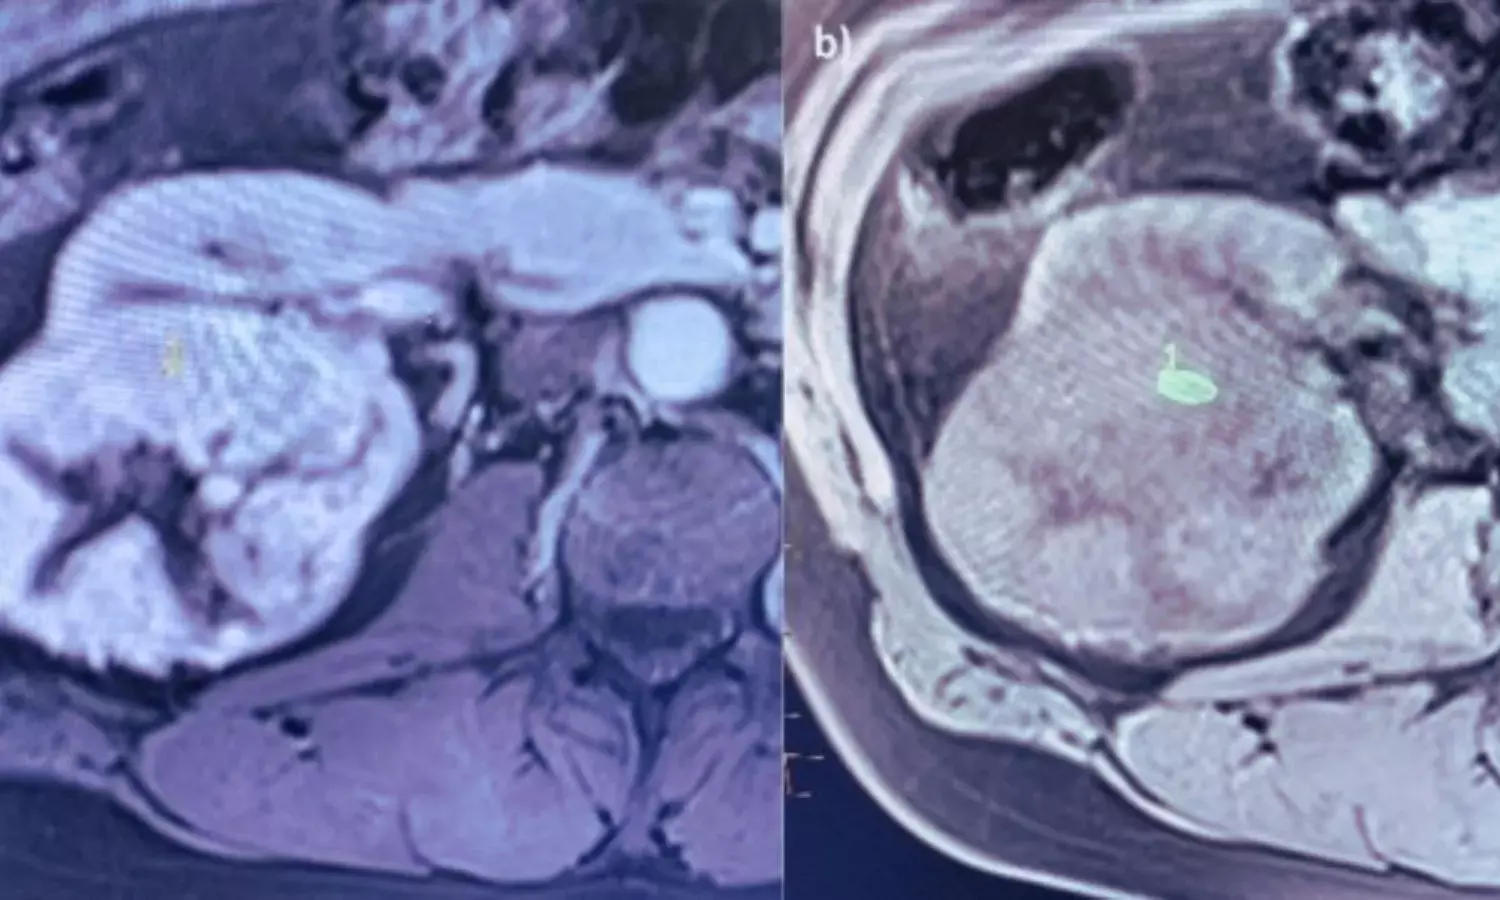

The study enrolled 43 patients (13 women, average age 59 ± 12 years) scheduled for nephrectomy. Each underwent a 1.5-tesla MRI scan that included diffusion-weighted imaging (DWI) with nine b-values, T1-mapping, multi-echo gradient-echo blood-oxygen-level-dependent imaging (BOLD), and dynamic-contrast-enhanced MRI (DCE-MRI). The team also calculated a clinical CKD risk score for each patient based on age, baseline kidney function, diabetes status, and type of surgery.

The researchers analyzed multiple mpMRI parameters, including cortical and medullary apparent diffusion coefficient (ADC), intravoxel incoherent motion, tri-exponential diffusion components, spectral diffusion, native T1, R2* from BOLD, and renal plasma flow from DCE-MRI. These measures were evaluated for their correlation with baseline kidney function, their ability to predict a postoperative 12-month decline in estimated glomerular filtration rate (eGFR) of more than 5 mL/min/1.73 m², and progression to stage III CKD (eGFR < 60 mL/min/1.73 m²).